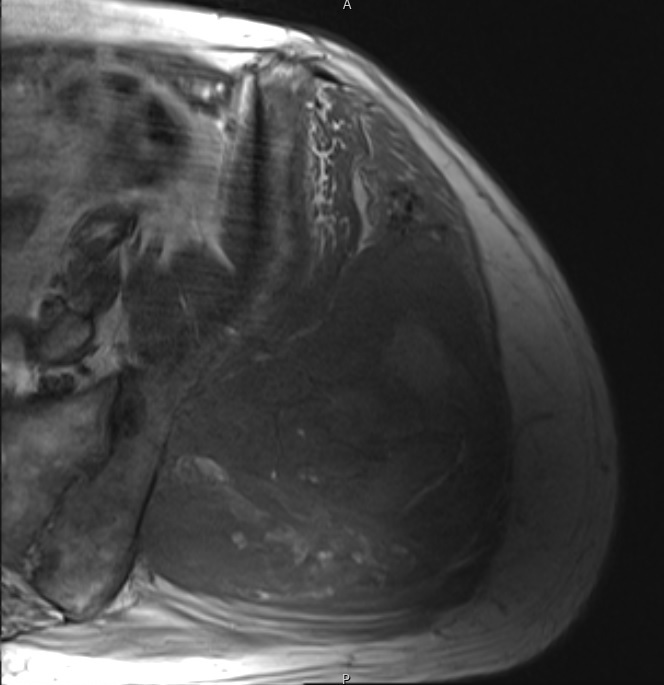

Fig. 1 & 2 Magnetic Resonance Image shows a large heterogeneous mass in the left gluteal region with low intensity signal on Axial (Fig. 1) and Coronal (Fig. 2) T1-weighted images admixed with some high signal areas indicative of fatty tissue. Higher intensity signal is visible compatible with hemorrhage or necrotic tissue. The mass involve the central portion of the left iliac bone.

Fig. 3 Axial fat suppressed T2-weighted MR image demonstrates a large heterogeneous mass with multiple thick internal trabeculations. Fatty areas suppress on T2 weighted fat suppressed areas